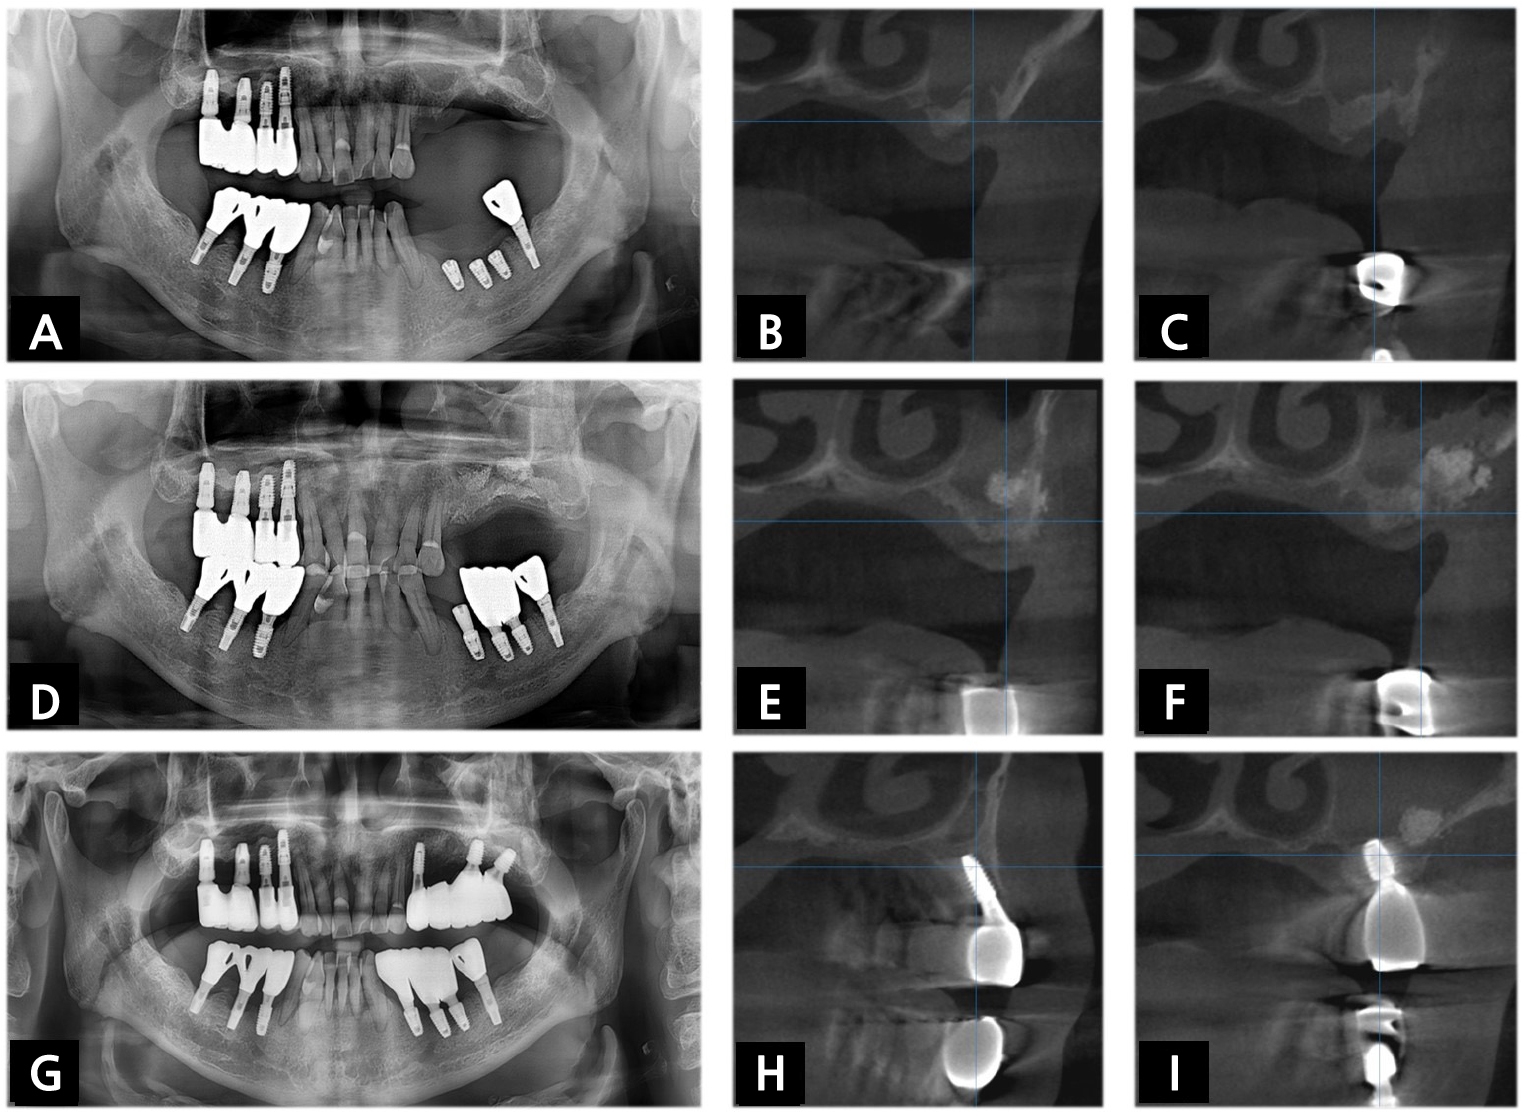

A 68-year-old male (patient 2) was referred to the Department of Oral and Maxillofacial Surgery to evaluate maxillary sinus disease and dental implant placement on the left posterior maxilla. Radiographic examination revealed complete opacity and approximately 2~4mm of available bone height in the left maxillary sinus (Fig. 2A to 2C). Because the suspicious chronic maxillary sinusitis was asymptomatic, despite a detailed explanation, the patient stubbornly refused referral to the Department of Oral and Maxillofacial Surgery or Otolaryngology in a hospital setting for further evaluation and treatment of ostium patency and asked for the treatment of MSDs and implant placement in our clinic. After suggesting the possibility of referral and surgical intervention of the ostiomeatal unit enlargement in the future, medication, including antibiotics, anti-inflammatories and nasal decongestants, was prescribed three times a day for one week before surgery. Then, debridement of inflamed tissue was done via the lateral bone window, followed by simultaneous SALW with bone substitute. At four months after SALW, dental implants were placed on the left maxillary molar area after reduced mucosal thickening less than one-half of the maxillary sinus was identified in panoramic radiograph (PAN) and cone beam computed tomography (CBCT) (Fig. 2D to 2F). Eighteen months after delivery of the definitive prosthesis, CBCT revealed a recurrence of opacification in the left maxillary sinus. Though no symptom or sign of a chronic inflammatory condition was detected, it remains under surveillance (Fig. 2G to 2I).

Fig. 2.

(A) Preoperative PAN and (B, C) CBCT of patient 2 revealed complete opacification in the left maxillary sinus. Before the sinus augmentation, (D) Follow-up PAN and (E, F) CBCT revealed reduced mucosal thickening in the left maxillary sinus. (G) Postoperative PAN and (H, I) CBCT demonstrated recurred opacification in the left maxillary sinus 18 months after delivery of the definitive prosthesis.